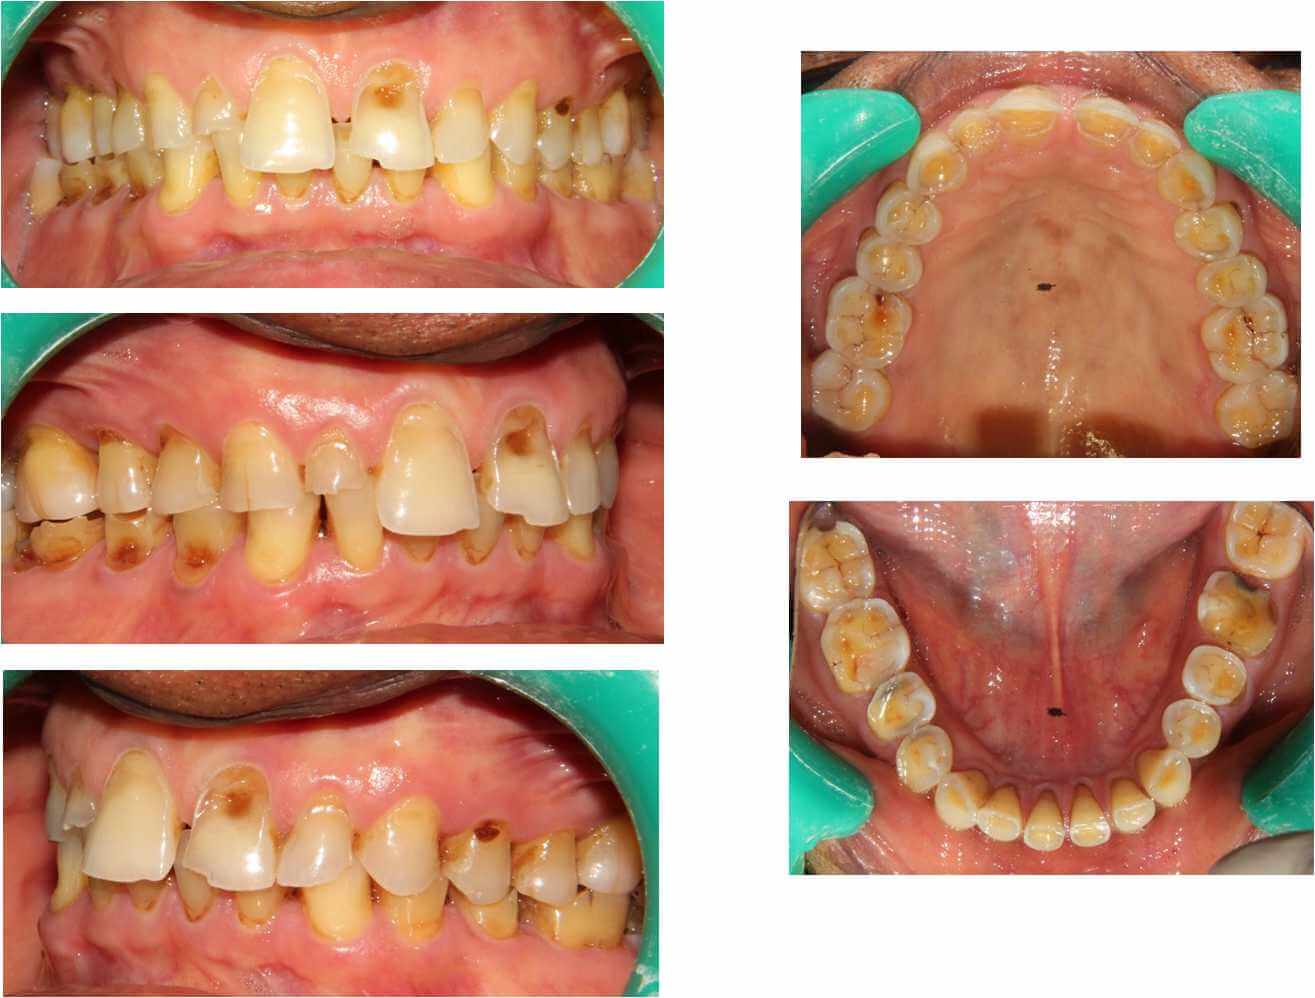

- Short, worn teeth

- Chipped and broken throughout the mouth

- Loose teeth

- Tobacco chewers whose teeth are reduced in height